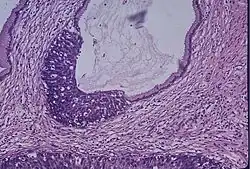

Breast cancer is the most common cancer for women.[23] Screening is done to detect the disease early in asymptomatic women, in an attempt to achieve an earlier diagnosis and lower mortality. Different screening tests are used for breast cancer screening, including clinical and self-examination of the breasts, mammography, and magnetic resonance imaging (MRI). Mammography is the standard method for breast cancer screening. This method is reported to give a 40% reduction in the risk of dying from the disease.[24] Breasts with less fat and more fibrous tissue are known as dense breasts, they are a risk factor for breast cancer. The tissue makes it harder to find tumors while doing a mammogram, therefore MRI screening is proposed to supplement the mammogram in these patients.[24]